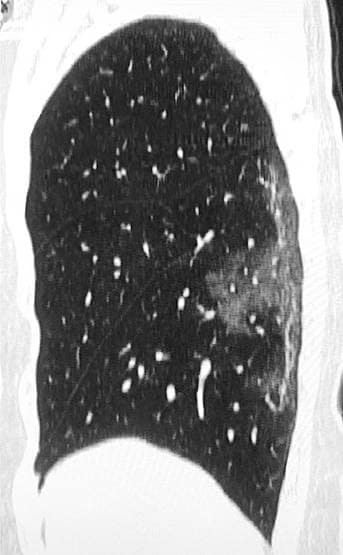

छाती में म्यूकस बनने की वजह से सांस लेने में दिक्कत आती है. साथ ही छींक आती है. क्योंकि आपको सांस लेते समय पर्याप्त हवा नहीं मिलती. इस एक्स-रे को देखकर ऐसा लगता है कि इन मरीजों के फेफड़ों में हवा की जगह सफेद मौत भरी हुई है. (फोटोः पीटीआई)